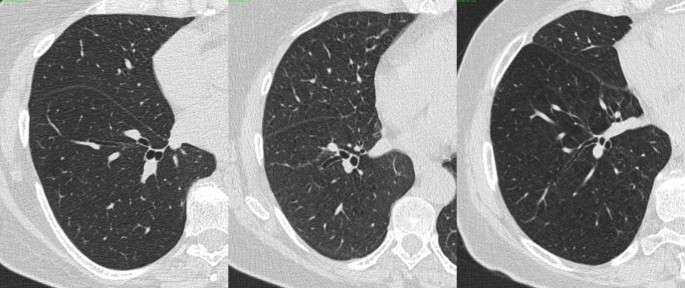

Image Contrast, Noise, Resolution

Image Contrast, Noise, Resolution from image.slidesharecdn.com